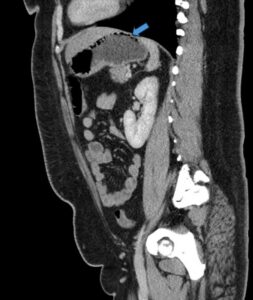

Gastric Emphysema. Sagital CT, annotated. JETem 2024

Gastric Emphysema. Sagital CT annotated. JETem 2024